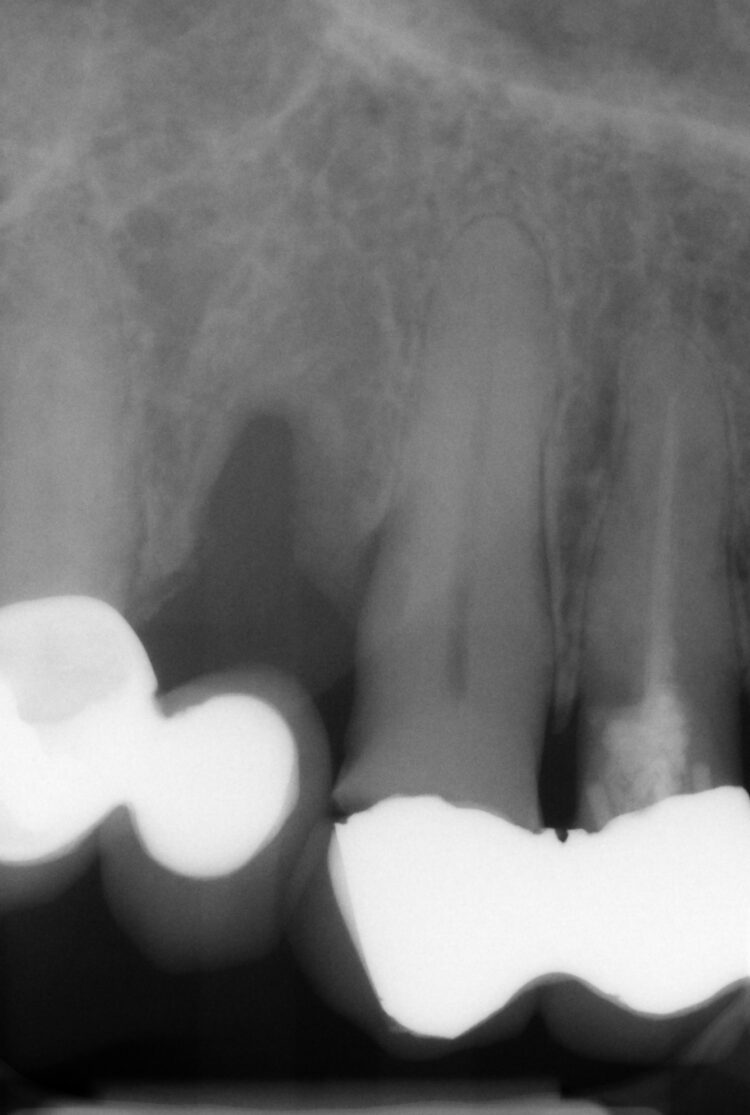

A comprehensive clinical assessment was conducted to evaluate the potential treatment options. A full suite of clinical photographs was taken to assess the aesthetics, with x-rays to better understand the damage to the remaining teeth. A CT scan was also required to assess the existing bone volume.

Despite using all the available examination tools, it was still challenging to assess the level of damage to the teeth under the metal ceramic bridge, because the prosthetic material obstructed the x-ray. It was confirmed that two teeth were decayed and fractured, but it was not possible to confidently diagnose the UR2.

The UR2 was assessed and deemed unrestorable. The UR2, UL2 and 3 were then extracted as minimally traumatically as possible.

The two 3.3mm diameter Tapered Pro Conical implants were then placed through the guide at the pre-determined positions, angles and depths. Both implants achieved an insertion torque above 30Ncm.